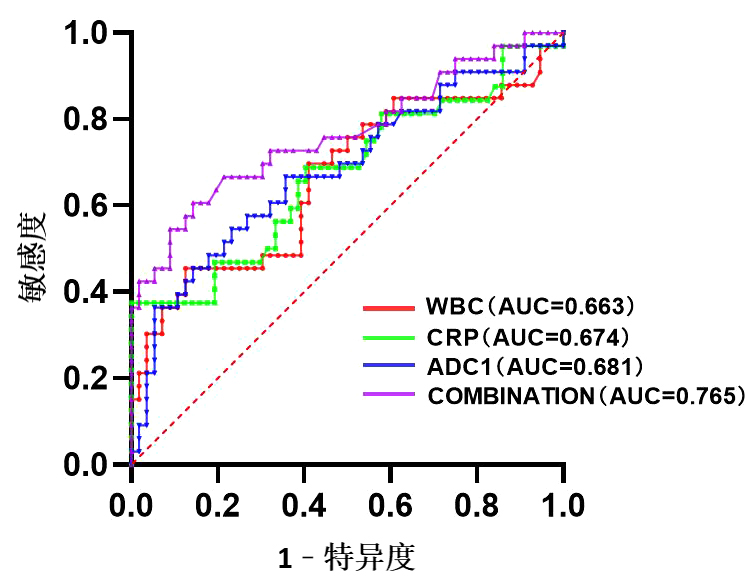

半卵圆中心ADC值与CRP联合的AUC为0.765(95%CI: 0.656~0.845),特异度87.9%,敏感度23.2%,界值3.5°。半卵圆中心ADC值联合CRP对DEACMP的早期诊断较单一WBC、CRP、半卵圆中心ADC更具临床价值。见图 2和表 3。

| WBC为白细胞计数,CRP为C-反应蛋白,ADC为半卵圆中心ADC值,COMBINATION为CRP与半卵圆中心ADC值联合预测因子 图 2 不同指标对DEACMP预测价值的ROC曲线 Fig 2 ROC of different indexes for the predictive value of DEACMP |

| 指标 | AUC | 95%CI | 截断值 | 敏感度(%) | 特异度(%) | 最大约登指数 |

| WBC(×109/L) | 0.663 | 0.539~0.787 | 6.80 | 45.5 | 87.5 | 0.330 |

| CRP(mg/L) | 0.674 | 0.550~0.797 | 6.68 | 36.4 | 100.0 | 0.364 |

| 半卵圆中心ADC(×10-3mm2/s) | 0.681 | 0.562~0.802 | 719.98 | 30.3 | 87.5 | 0.305 |

| CRP与半卵圆中心联合预测因子 | 0.765 | 0.656~0.845 | 3.50 | 23.2 | 87.9 | 1.440 |

| 注:WBC为白细胞计数,CRP为C-反应蛋白,ADC为表观扩散系数 | ||||||